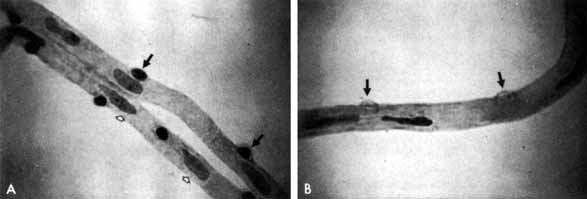

Although microaneurysms are the first ophthalmoscopically detectable change in diabetic retinopathy, the earliest abnormalities seen histopathologically are thickening of the capillary basement membrane1,2 and pericyte dropout.3,4 Pericytes are mesothelial cells that surround and support the retinal capillary endothelial cells. Normally there is one pericyte per endothelial cell. In people with diabetes, however, the pericytes die off and are decreased in number (Fig. 1). Their absence weakens the capillaries and permits thin-walled dilatations, called microaneurysms, to develop. Later, endothelial cells proliferate and lay down layers of basement membrane material. Fibrin may accumulate within the microaneurysm along with erythrocytes, and the lumen of the microaneurysm may become occluded (Fig. 2). Initially, most microaneurysms are on the venous side of the capillaries, but later they are seen on the arterial side as well. Clinically, they appear as small red dots (Fig. 3). Despite the multiple layers of basement membrane, microaneurysms are permeable to water and large molecules, allowing the transudation of fluid and lipid into the retina.

Fig. 1 A. Trypsin digest preparation of early background retinopathy. Normal retinal capillaries, with one pericyte (closed arrows) per endothelial cell (open arrows). B. Retinal capillary of a patient with diabetes with necrotic pericytes (arrows). (Courtesy of Dr. Myron Yanoff)